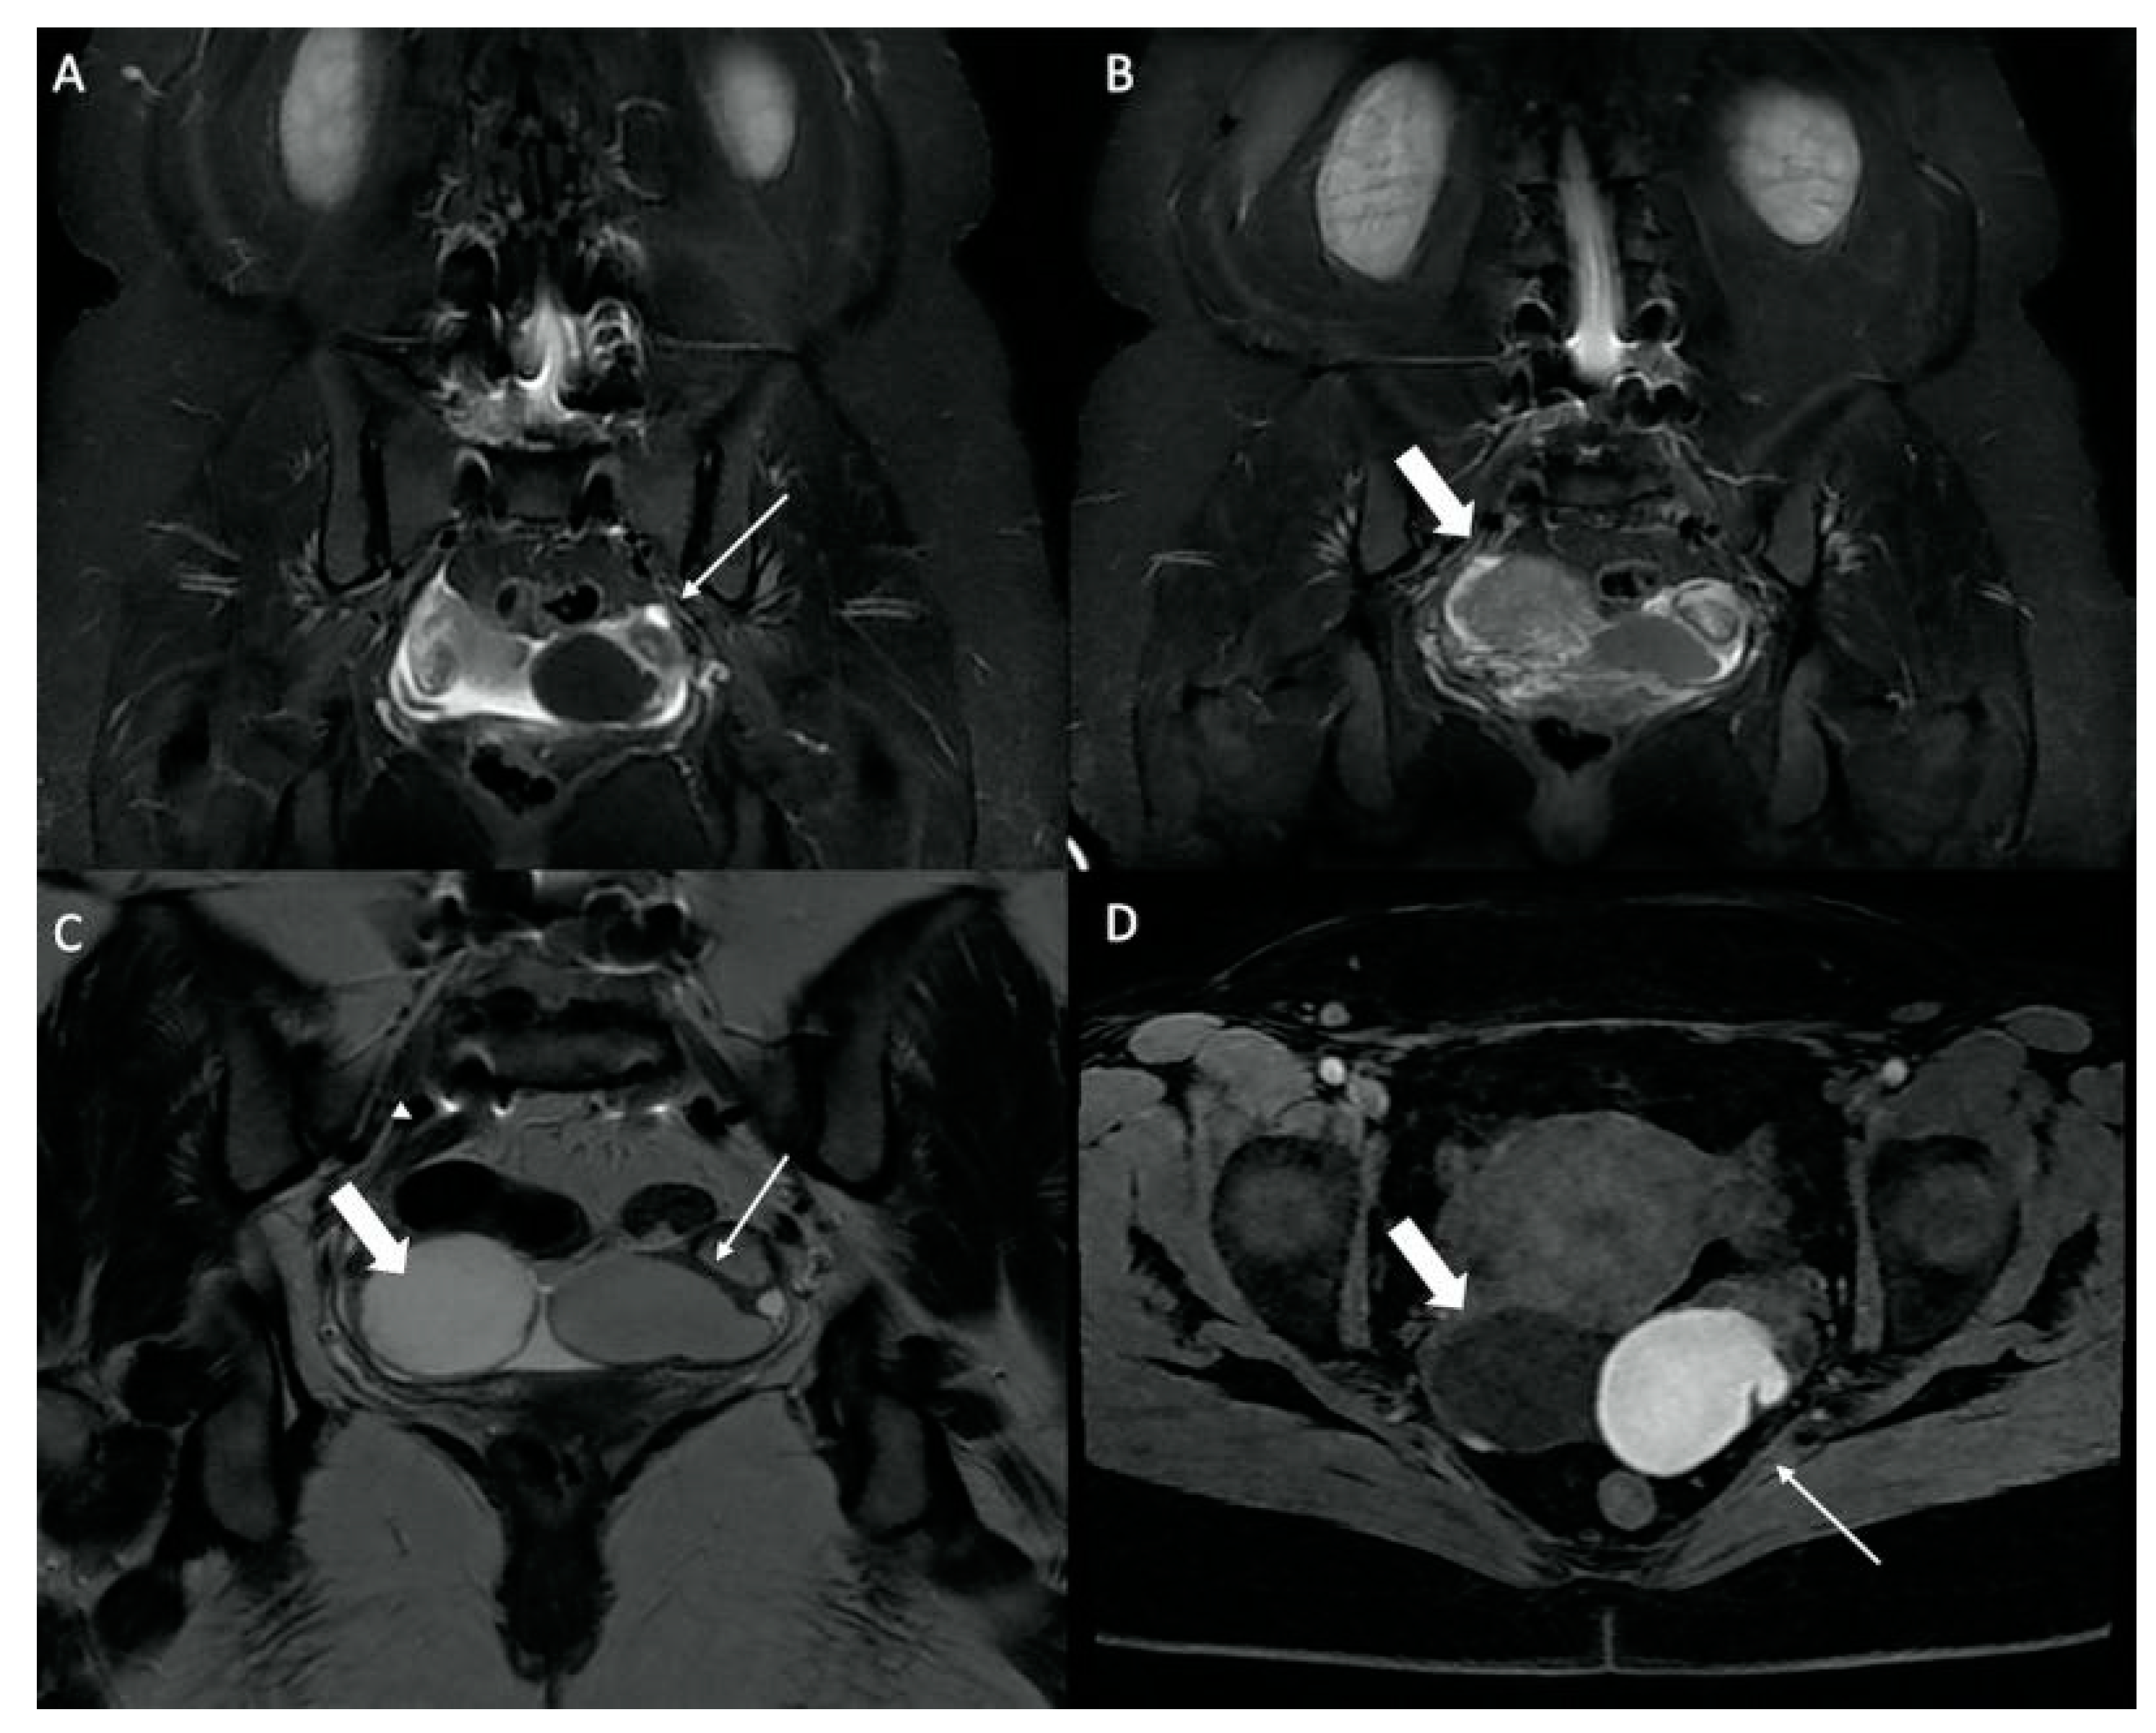

| Gluteal Muscles | Gluteal tendinobursitis | 21 |

| Sacroiliac Joint | Congestive degenerative arthropathy | 10 |

| Inflammatory sacroiliitis | 4 | |

| Sacral fracture | 1 | |

| Others | Endometrioma with posterior deep pelvic endometriosis | 1 |

| Ischio-femoral impingement | 1 | |

| Retroperitoneal mass syndrome with urinary obstruction | 1 |